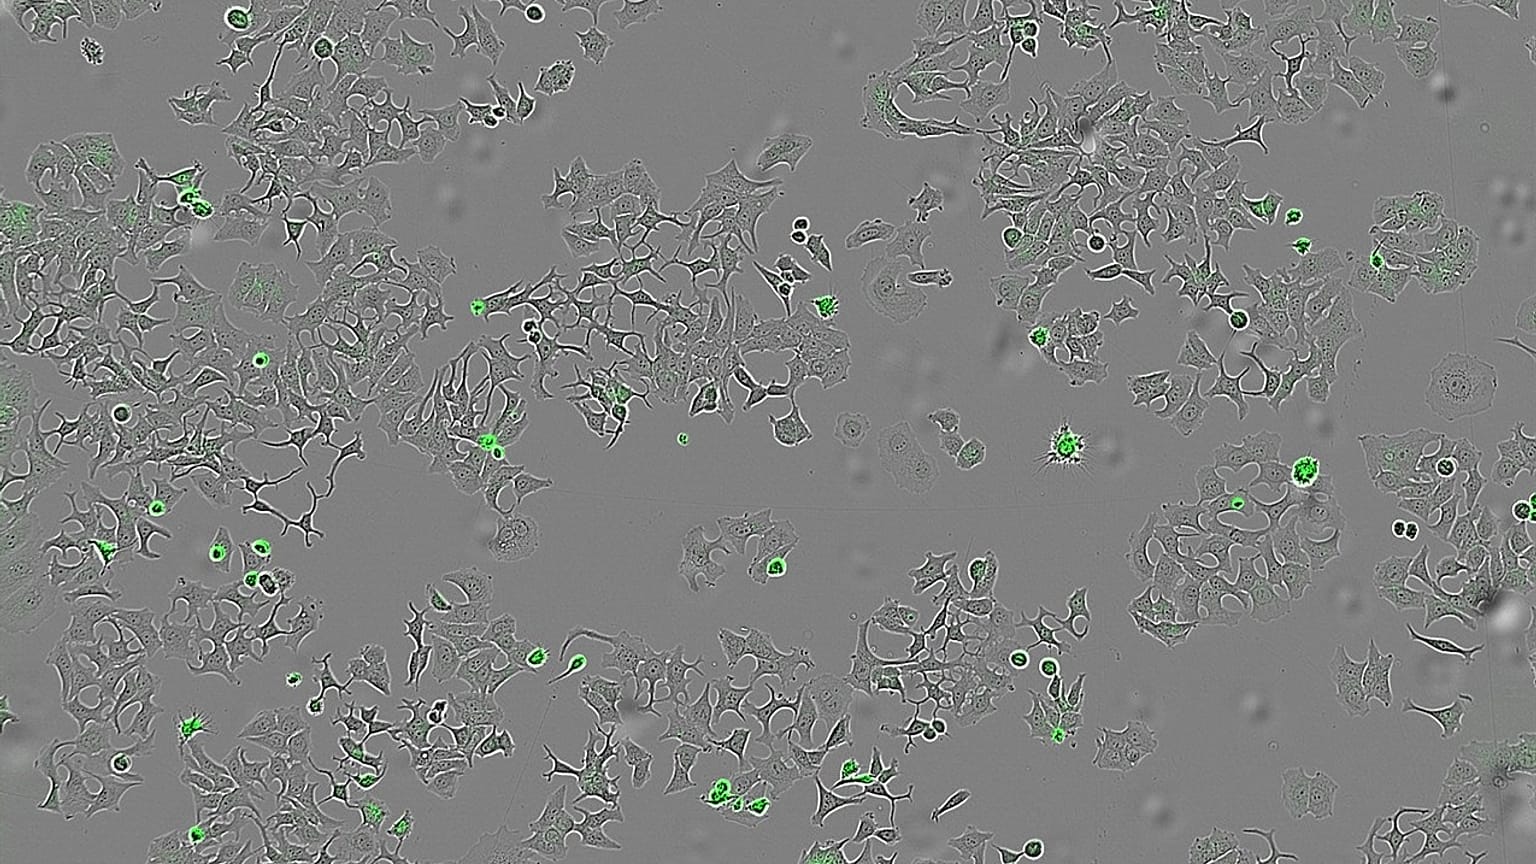

Imagen de células tumorales atacadas por la bacteria del cólera

Imagen de células tumorales atacadas por la bacteria del cólera Derechos de autor  CSIC

El sistema Incucyte® de imagen en vivo permitió monitorizar durante días la proliferación celular, la apoptosis y la viabilidad en tiempo real, proporcionando evidencia robusta del efecto antitumoral de HapA. Los experimentos demostraron que la activación de MEK-ERK por HapA es temprana (detectable a los 20 minutos) y transitoria (retorna a niveles basales a los 40 minutos), pero suficiente para iniciar la muerte celular programada.